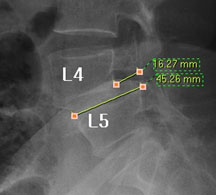

모커리한방병원 함○○ (55, 여) 척추전방전위증 2단계 실제치료사례 이미지

함○○ (55, 여) 척추전방전위증 2단계 입원치료기간 : 30일

입원시 퇴원시

허리 통증지수(NRS) 7 1

엉덩이 통증지수(NRS) 7 1

통증없이 걷는거리(m) 20m

(보조기 착용하고 하루 1회)

100m

(보조기 없이 하루 수회 각각)